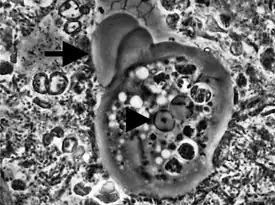

Существует только в форме трофозоита (вегетативная форма). Размеры колеблются от 6 до 60 мкм. Питается бактериями, образующими зубные камни, и клеточным детритом. Цитоплазма чётко разделена на два слоя, где можно рассмотреть фагоцитированные бактерии на разных стадиях пищеварения, при кровотечении из дёсен ротовая амёба может захватывать и эритроциты. Никогда не поглощает лимфоциты, что считается дифференциальным отличием от дизентерийной амёбы Entamoeba histolytica, особенно при совместном выделении из мокроты пациентов с лёгочными амёбными абсцессами. Цист не образует. Ядро живой амёбы не визуализируется. Движение медленное, ложноножки широкие.